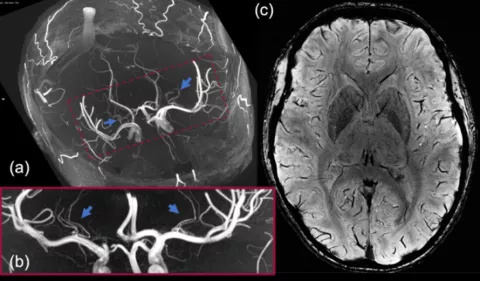

MRI scan images of tiny arteries in the brain which may become blocked and cause small strokes in people with sickle cell disease

The 7T scanner can create significantly more detailed images than a standard scan, including showing the blood flow in tiny arteries which would usually be invisible on hospital scanners.